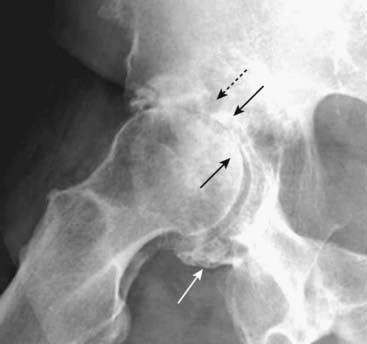

Figure 23-9 Charcot arthropathy of knees.

As a hypertrophic arthritis, a Charcot joint will demonstrate extensive subchondral sclerosis. The hallmark findings of a Charcot joint, however, are fragmentation of the bones surrounding the joint, which produces numerous small, bony densities within the joint capsule (solid white arrows) as well as joint space destruction (solid black arrows). The most common cause of a Charcot joint of the knee is diabetes.

Figure 23-10 Charcot arthropathy of foot.

This patient had previously undergone an amputation of the phalanges of the second toe (solid white arrow) for diabetic gangrene but the destruction and marked fragmentation of the great toe are manifestations of Charcot neuropathy (solid black arrows). Charcot neuropathy can produce some of the most dramatic examples of total joint destruction of any arthritis.